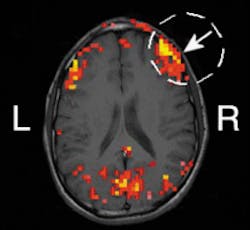

Researchers at the University of Illinois (UI; Champaign, IL) are exploring the use of frequency-domain near-infrared spectroscopy (NIRS) as a noninvasive diagnostic tool to study changes in human brain activity. In one experiment, they demonstrated a correlation between hemodynamic (blood-flow-related) signals at the surface of the brain obtained with both NIRS and functional magnetic resonance imaging (MRI)—the standard technique used in brain activation studies. Based on the results, UI physics professor Enrico Gratton believes NIRS shows promise as a way to study brain activity without performing surgery on the skull (see figure). As another benefit, the technique is both simpler to use and less expensive than functional MRI and other noninvasive methods such as positron emission tomography.

To validate the technique, Gratton and Vladislav Toronov, a researcher at the university's Beckman Institute for Advanced Science and Technology, compared hemoglobin oxygen concentrations in the brain using signals obtained simultaneously by NIRS and functional MRI. "Both methods were used to generate functional maps of the brain's motor cortex during a periodic sequence of stimulation by finger motion and rest," explained Gratton. "We demonstrated spatial congruence between the hemoglobin signal and the MRI signal in the motor cortex related to finger movement."

In the research project supported by the National Institutes of Health, the researchers also demonstrated collocation between hemoglobin oxygen levels and changes in scattering due to brain activities. "By having a volunteer move different fingers, we could see an increase in perfusion in different areas of the brain," Gratton reported. "The changes in scattering associated with fast neuron signals came from exactly the same locations."